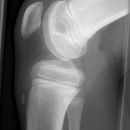

Tibiakopf

Tibiakopf 16 Jahre alt